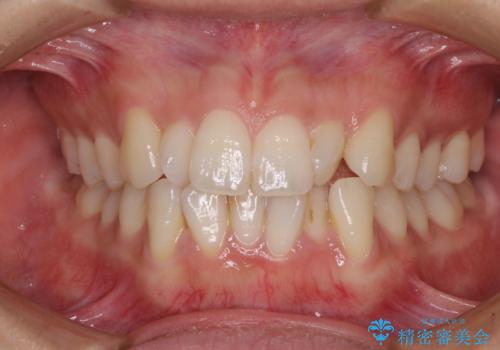

- 上下前歯のねじれを気にして来院された患者様です。

ワイヤー矯正でもマウスピース矯正でも対応可能でしたが、マウスピース矯正の自己管理が面倒であること、上顎前歯の捻転が著しいことから、ワイヤー矯正での治療を希望されました。